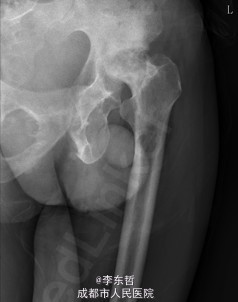

患者男,62岁,因“双髋疼痛4年,加重伴活动受限1年”入院。病员诉入院前4年无明显诱因出现双侧髋部疼痛,行走后疼痛加重,疼痛能忍受,双侧髋部无红肿,皮温不高,无畏寒、发热,休息后疼痛能自行缓解,无夜间疼痛,在当地医院行止痛药内服、理疗治疗,疼痛稍缓解。逐渐加重,1年前双侧髋部疼痛、跛行明显加重,左髋活动受限,行走困难,给予对症治疗症状无明显改善,遂到我科门诊就诊,X线片提示:双侧股骨头坏死,建议手术治疗,故于今日以“双侧侧股骨头坏死”收入我科进一步治疗。

查体:生命体征平稳,心肺腹未见异常;跛行,双左下肢较右下肢短缩1cm,左、右腹股沟中点深压痛,左、右髋叩击痛,左髋屈20°,伸0°,外展10°,内收10°,右髋屈60°,伸0°,外展20°,内收20°。双髋内、外旋活动受限,诱发疼痛,左侧重。 辅助检查:x线片示双侧股骨头坏死、塌陷变形,左侧明显,左髋半脱位。

初步诊断:1、左侧股骨头坏死伴内收肌挛缩(Ficat IV期);2、右侧股骨头坏死(Ficat IV期);3、右膝骨关节炎伴外翻畸形;入院后积极完善术前检查及准备,择期行手术治疗。